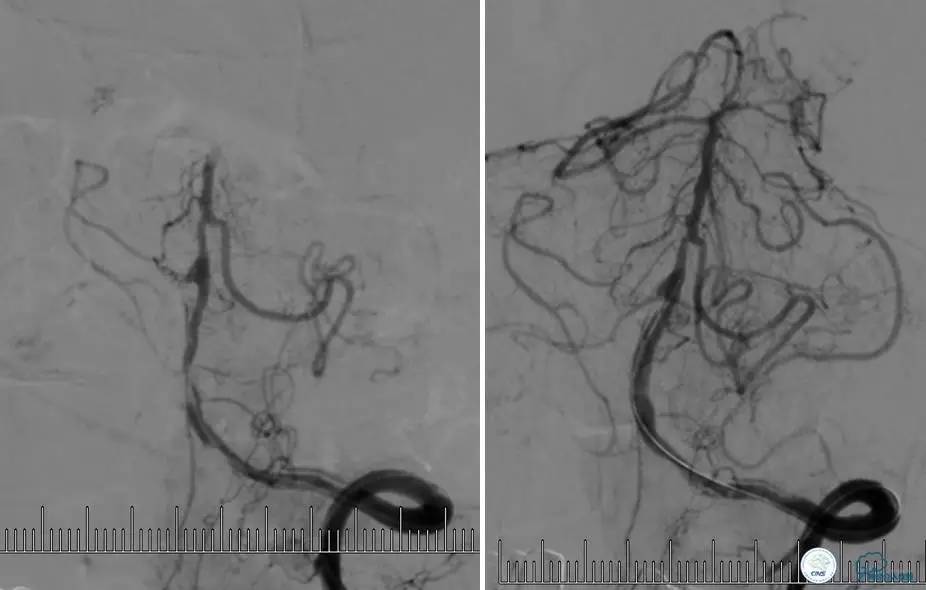

病例7

患者:反复发作右侧肢体无力、言语不清15天。

导丝很容易通过闭塞段。

顺利置入Wingspan支架,成功开通,手术顺利。